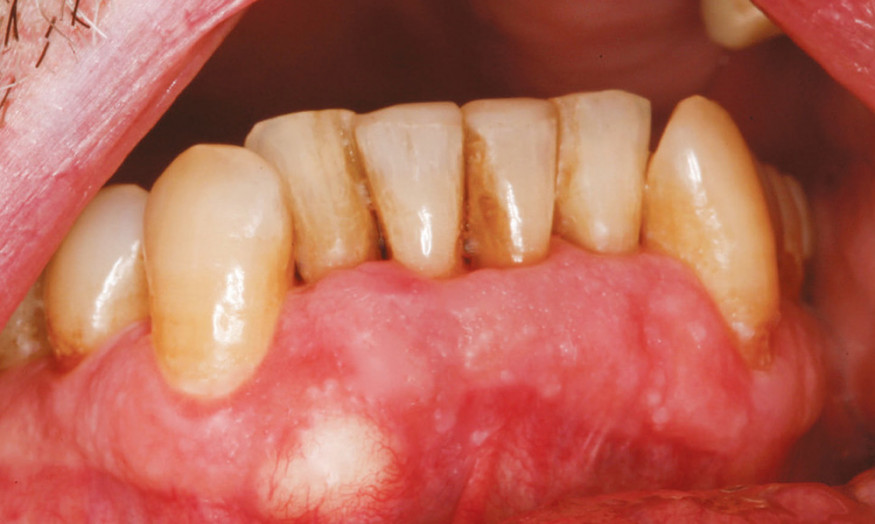

Motif de la consultation. Patient de 72 ans venu consulter sur les conseils de son hygiéniste dentaire [la prise en charge se déroule en Suisse, Ndlr] qui a remarqué la présence d’une tuméfaction gingivale vestibulaire.

Examen clinique. La tuméfaction se traduisait par une masse jaunâtre, oblongue, de 10 x 7 mm, siégeant sur la limite inférieure de la fibromuqueuse ginigivale vestibulaire entre les racines de 42 et 43. Il n’y avait aucun signe inflammatoire d’accompagnement. La palpation de la tuméfaction, non douloureuse, révélait une collection liquidienne associée à une déhiscence osseuse s’étendant surtout vers le fond du vestibule ; la corticale osseuse autour de la déhiscence n’était pas soufflée.